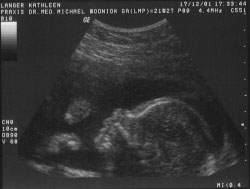

So sah ich am 17.12.2001 aus. Mama war in der 22. Schwangerschaftswoche (6.Monat).

Mama und Papa freuen sich immer ganz sehr, wenn ich mit ihnen spiele und sie meine Tritte merken... Seht Ihr wie ich meine Händchen schon zur Faust ballen kann? Wie ein kleiner Boxer, oder? Hier bin ich jetzt schon ca. 28 cm groß...